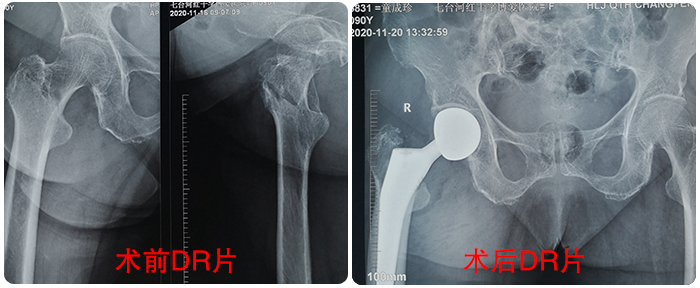

童奶奶術(shù)前術(shù)後對(duì)比影(yǐng)像